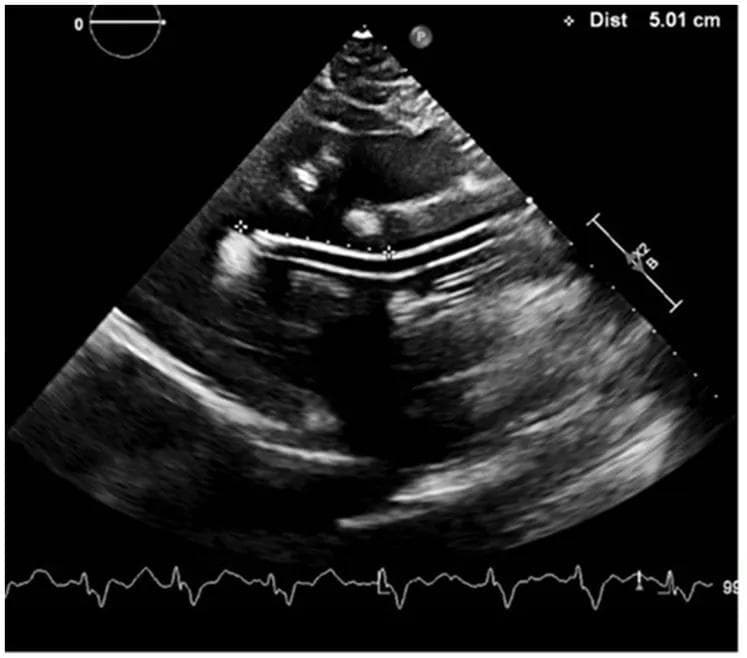

Особен акцент беше поставен върху имплементирането на Impella 5.5 - съвременна механична циркулаторна поддръжка. Това е миниатюрна помпа, която се въвежда през голям съд (най-често аксиларна артерия) и подпомага директно лявата камера, като изпомпва кръв към аортата. Устройството се използва при тежка сърдечна недостатъчност или кардиогенен шок и позволява временна хемодинамична стабилизация и „разтоварване“ на сърцето след високорискови операции.